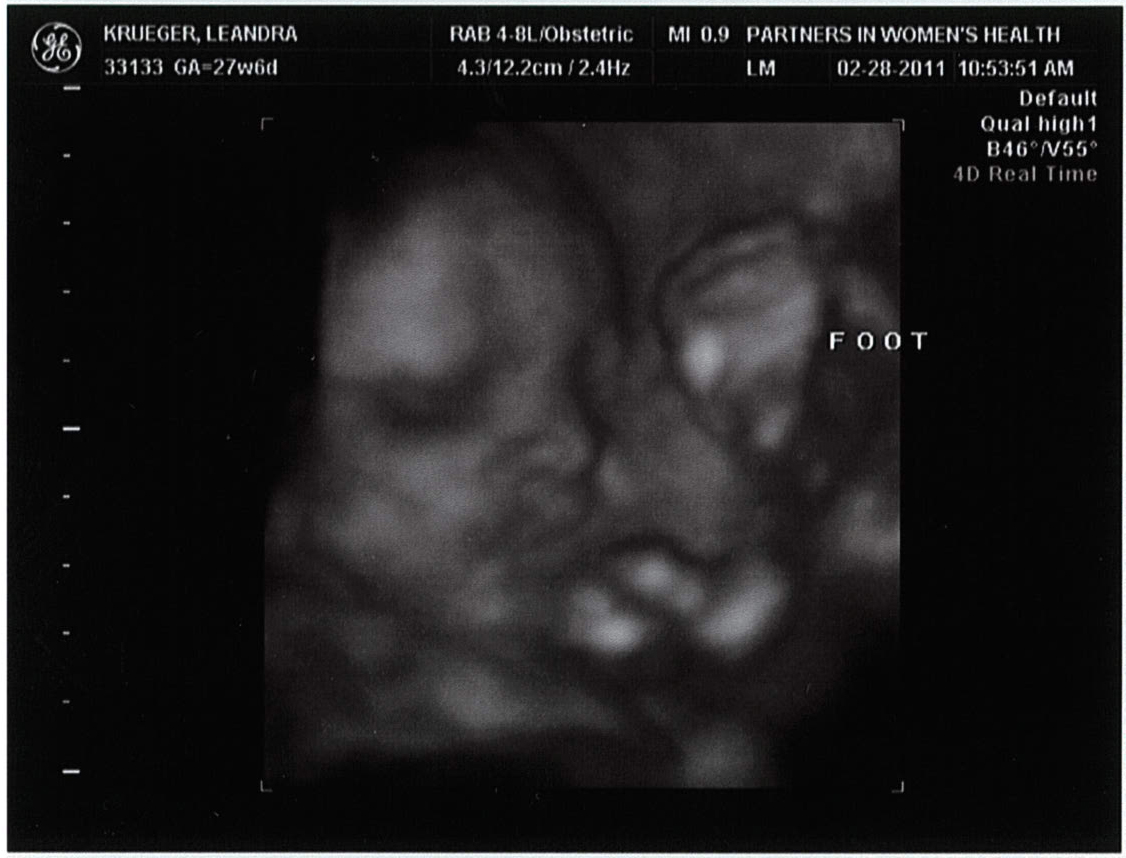

BABY KRUEGER FACE + FOOT (flexible)